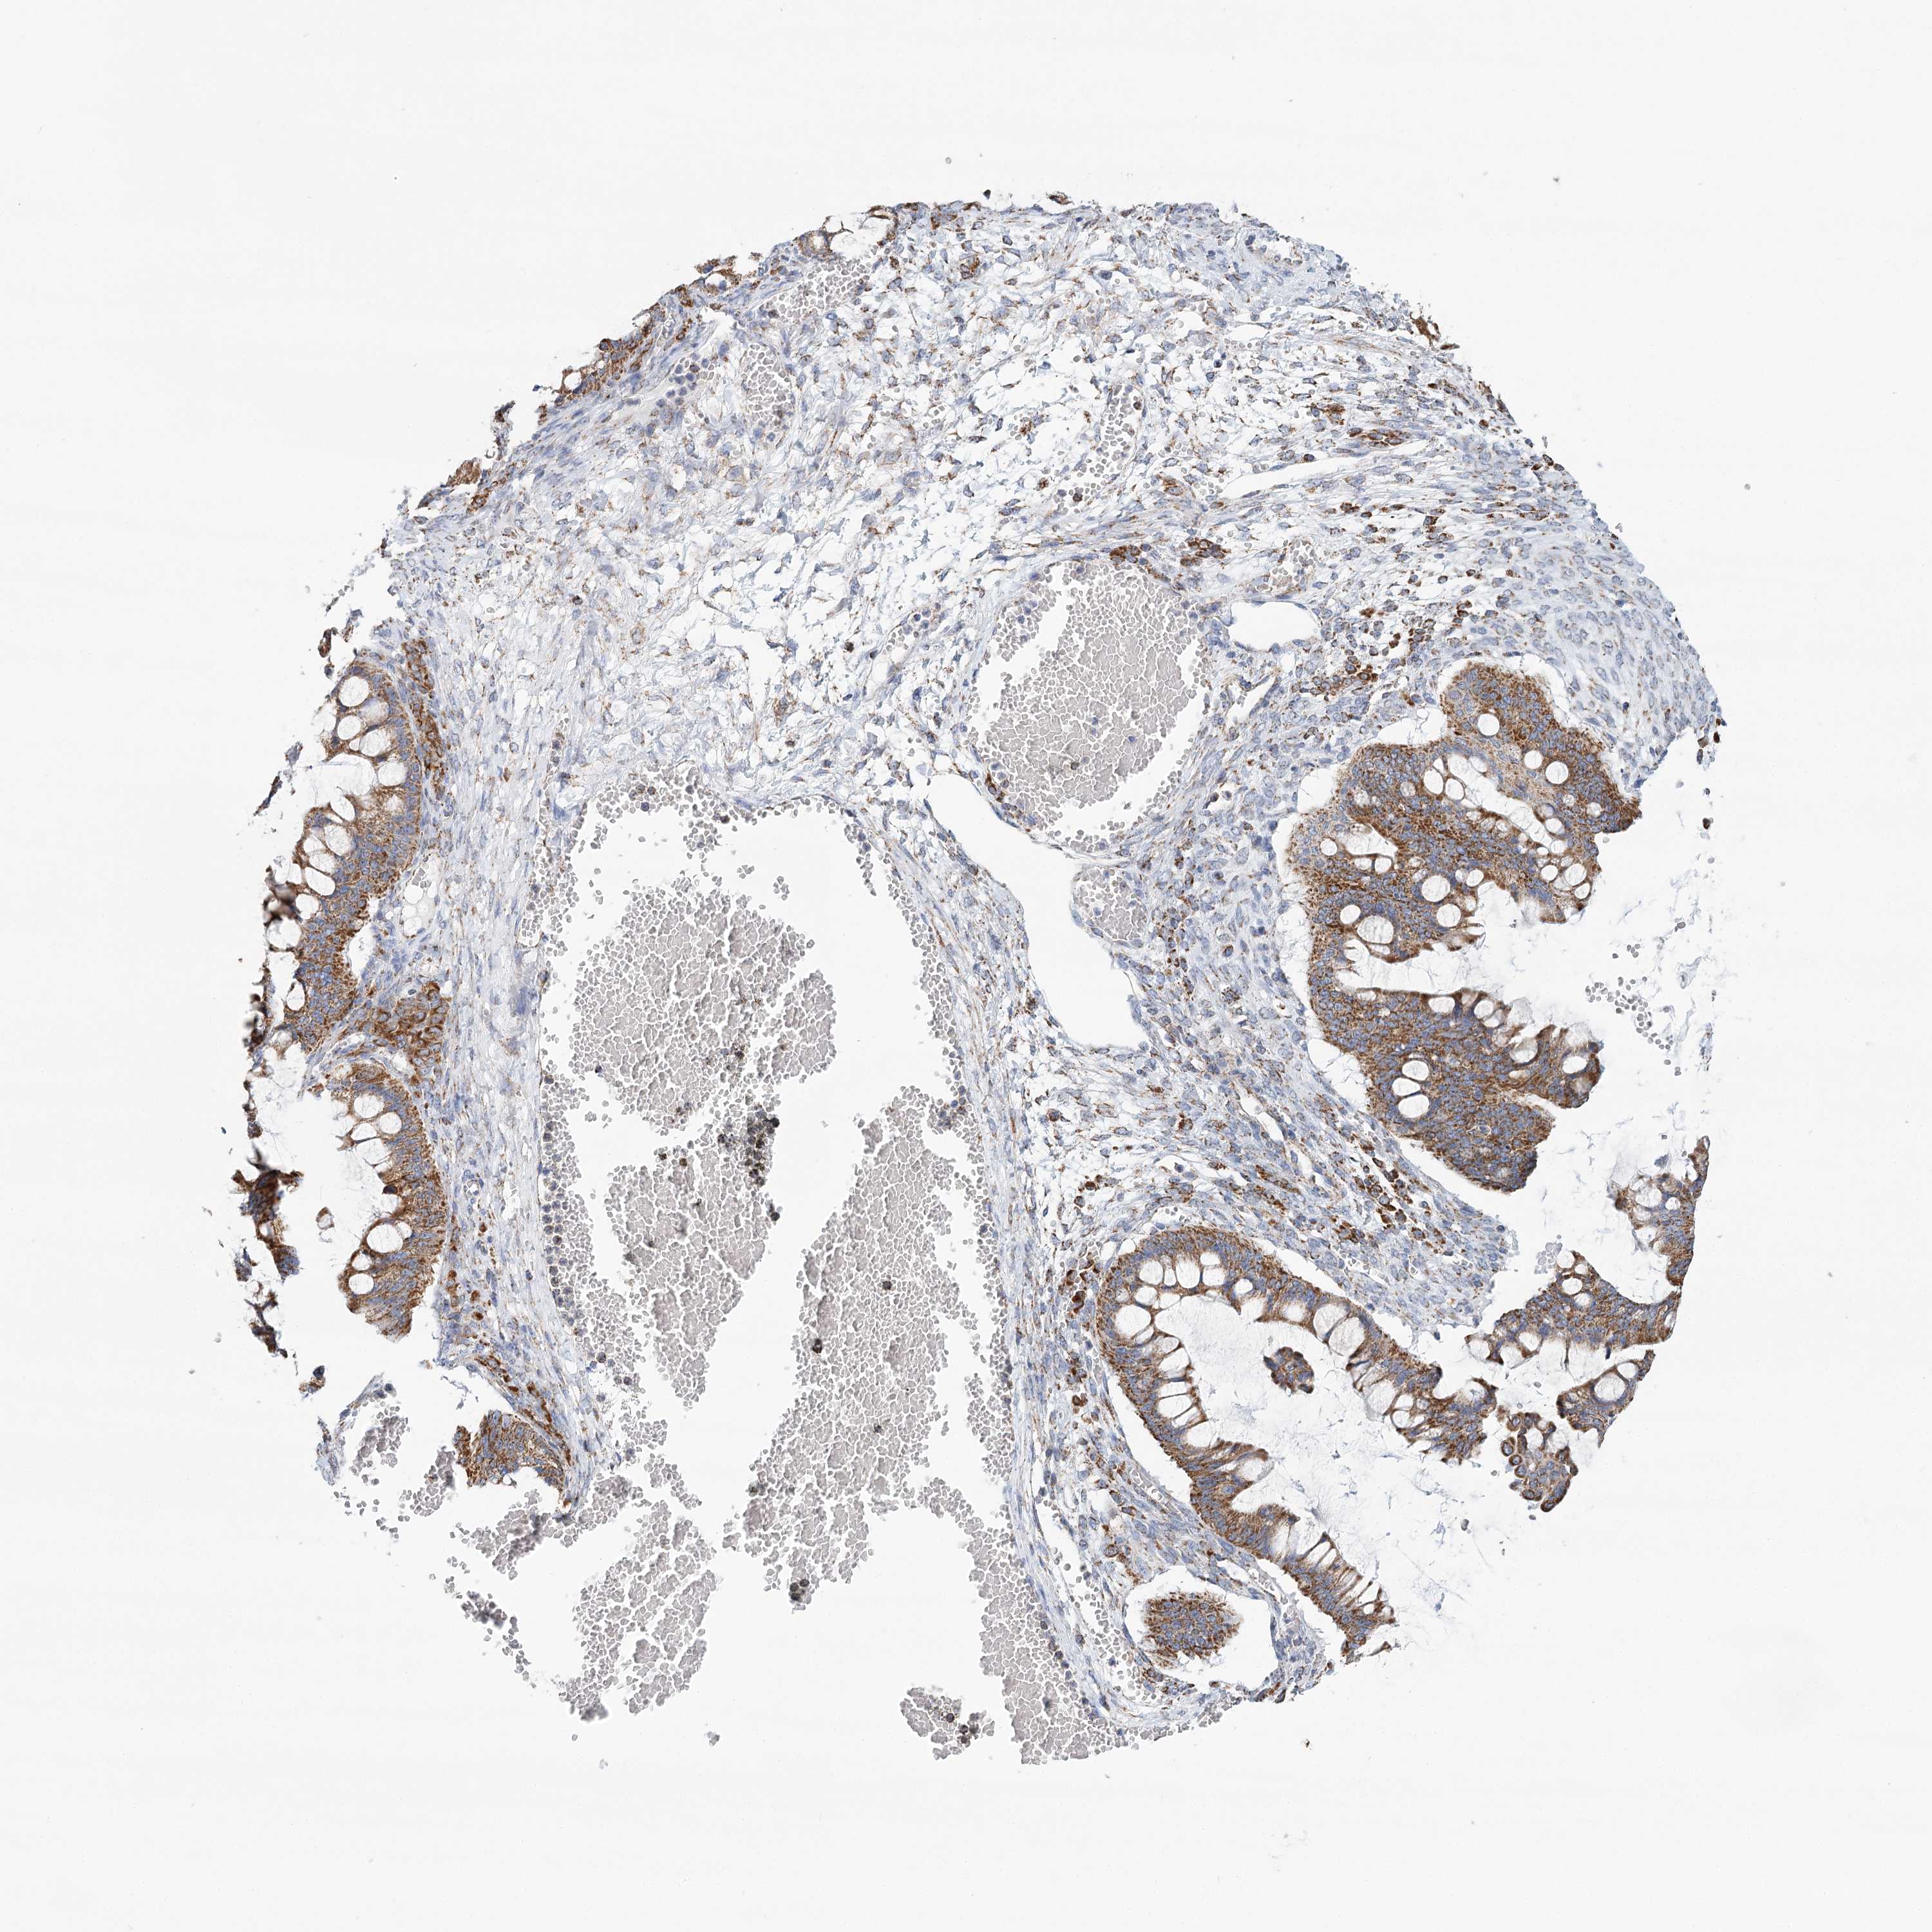

OVARIAN CANCER - Protein expressioni

A mouse-over function shows sample information and annotation data. Click on an image to view it in a full screen mode. Samples can be filtered based on level of antibody staining by selecting one or several of the following categories: high, medium, low and not detected. The assay and annotation is described here.

Note that samples used for immunohistochemistry by the Human Protein Atlas do not correspond to samples in the TCGA dataset.

Antibody stainingi

Antibody staining in the annotated cell types in the current human tissue is reported as not detected, low, medium, or high, based on conventional immunohistochemistry profiling in selected tissues. This score is based on the combination of the staining intensity and fraction of stained cells.

Each image is clickable and will lead to virtual microscopy that enables deeper exploration of all samples and also displays staining intensity scores, fraction scores and subcellular localization as well as patient and tissue information for each sample.

Antibody HPA032060

Antibody HPA032062

Staining

High

Intensity

Strong

Quantity

Location

Cytoplasmic/membranous

Cystadenocarcinoma, serous, NOS

Carcinoma, endometroid